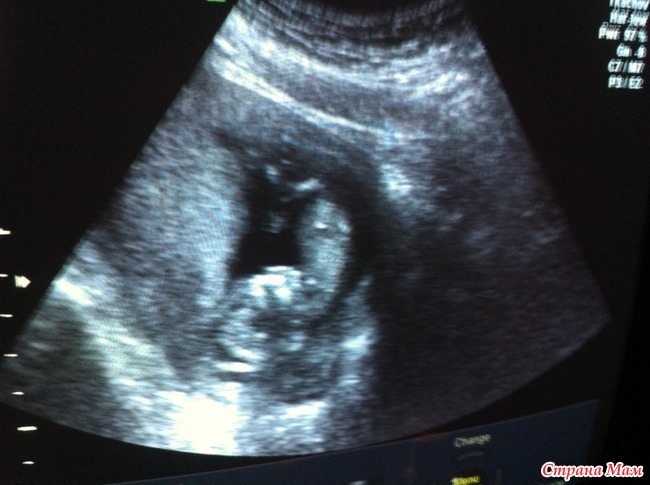

На прошлой неделе было наше первый скиннинг

Мы с мужем увидели нашу лялечку

, сразу, как только глянули, сказали, что похоже на парнишку (нам очень хочется мальчика). Наша лялечка была вниз головой, поджав ножки и ручками вверх, как меня не крутили поворачиваться он не хотел

Самое главное все хорошо, а это самое важное.Вот сегодня пошла сдаваться в свою консультацию... Почему никто не пишет, что это ТАКОЙ КАРАУЛ